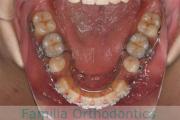

No.22V-211

- 上下顎前突

- 交叉咬合

- 17歳

- 女性

- 抜歯部位

- 上:

- non

- 下:

- 主な使用装置:

- Invisalign

- 治療にかかった費用:

- 90万円

奥歯の歯並び、特に7番のすれ違いを治して欲しいとのことで来院されました。特に左下の舌側への倒れこみが強い、叢生(でこぼこ、ガタガタ)の症例です。マウスピース型矯正装置の一つ、マウスピース型矯正装置のひとつ、インビザライン/Invisalign®(薬機法および医薬品副作用被害救済制度の対象外)を用いて治療を行いました。にて治療を行いました。2年弱、20回程度通院していただきました。インビザラインは、患者さんの使用状況により治療効果が上下してしまうリスクがあります。